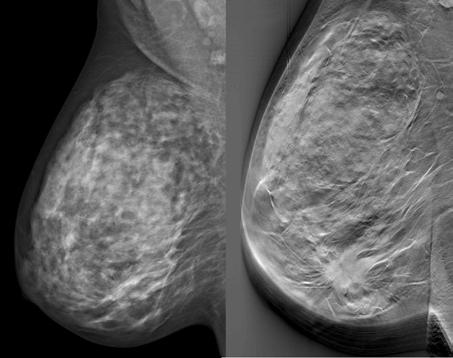

Röntgenbilder som jämför Isabellas lever. Levern ligger till vänster i bilderna. Bilden t.v. är från juli (innan TACE) och t.h. från oktober. Det vita är tumörer.”När du kom hit såg levern ut som en stjärnhimmel, nu har vi släckt ner en hel del”, säger Prof. Vogl.

de svenska periodiska röntgenutvärderingarna i höstas visade på stor regress, krympta och döda metastaser och små spår av behandlingen i levern. Och inga nytillkomna metastaser alls!